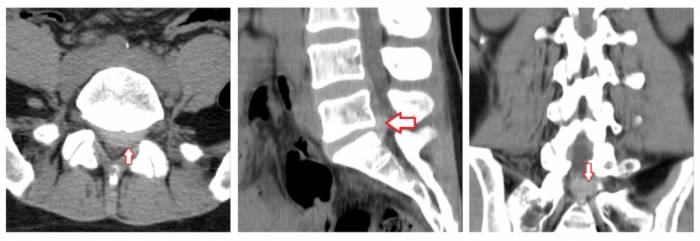

Грыжи межпозвонковых дисков при КТ позвоночникаклассифицируются в зависимости от их локализации. Так, выделяют задние, латеральные и передние грыжи дисков — в зависимости от того, в какую сторону выпадает межпозвонковый диск. Задние грыжи в свою очередь могут быть центральными (диск выбухает кзади по средней линии), медиаолатеральными (диск выбухает в латеральный карман справа либо слева), фораминальными (диск выбухает в межпозвонковый канал). Грыжа диска может быть также внутрикостной (по типу т. н. грыжи Шморля) — при этом происходит пролабированиепульпозного ядра в тело позвонка с проламыванием его замыкательной пластинки.Грыжа Шморля при компьютерной томографии позвоночника выглядит как дефект тела позвонка, отграниченный плотным склерозированным «ободком». Редко встречается также вариант интрадурального пролапса (грыжи), когда секвестр распространяется под твердую оболочку спинного мозга.

Пример медиолатеральной грыжи МПД в сегменте L4-L5, распространяющейся в латеральный канал. Грыжа диска при КТ визуализируется в виде гиперденсного объекта (край диска выбухает по дуге малого радиуса) в левую сторону, вызывая сдавление нервного корешка и выраженный болевой синдром.